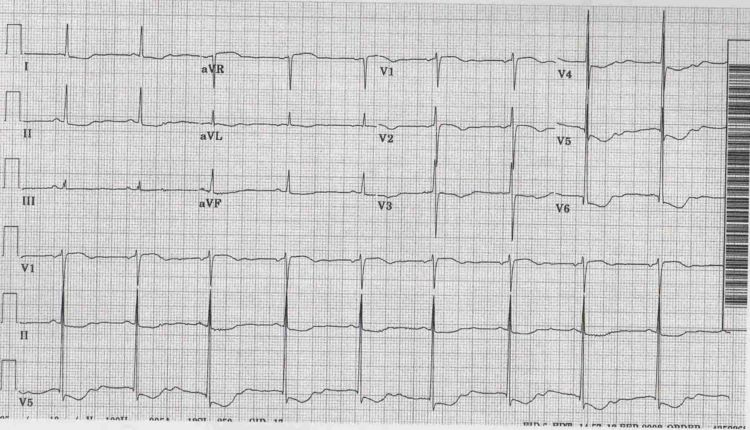

EKG abnormality of Hyperkalemia

ผู้ป่วยอาจมา present ด้วย EKG abnormality, arrthymia หรือ cardiac arrest ก็ได้ การที่จะมีอาการหรืออาการแสดงมากน้อยเพียงใด ขึ้นอยู่กับระดับของ Hyperkalemia  และ rate ของการเพิ่มขึ้นว่าเร็วเพียงใด ความผิดปกติเริ่มแรก จะเกิดขึ้นเมื่อ K > 5.5 mmol/L กล่าวคือ จะเห็นเป็น Symmetrical tall peaked T wave (ดังรูปแสดง EKG) แต่มีผู้ป่วยเพียง 20% เท่านั้นที่มี EKG ลักษณะเช่นนี้13 แต่เมื่อระดับ K สูงกว่า 6.7 mmol/Lโดยทั่วไปผู้ป่วยมักมี EKG เปลี่ยนแปลง อย่างไรก็ตามผู้ป่วยอาจมี EKG ปกติได้แม้ระดับ K จะสูงมากก็ตาม แต่ในกรณีนี้ ต้องแยกภาวะ Pseudo-hyperkalemia ออกไปก่อน

ระดับความไวต่อภาวะ Hyperkalemia ที่หัวใจ จะเกิดขึ้นตามลำดับจากมากไปน้อยดังนี้ : atrium, the ventricular cells, His cells, sinoatrial node และ inter-atrial tracts ดังนั้นรูปแบบการเปลี่ยนแปลงของ EKG จะเป็นไปดังตาราง  โดยอาจมีการ overlap ของ EKG pattern บ้างในแต่ละ severity ของ Hyperkalemia

ลักษณะ EKG ของ hyperkalemia

Tented T waves, loss of P waves and a wide QRS complex

a sinewave pattern

Bradycardia and tall peaked (tented) T waves